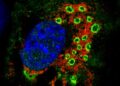

- Labs@Work